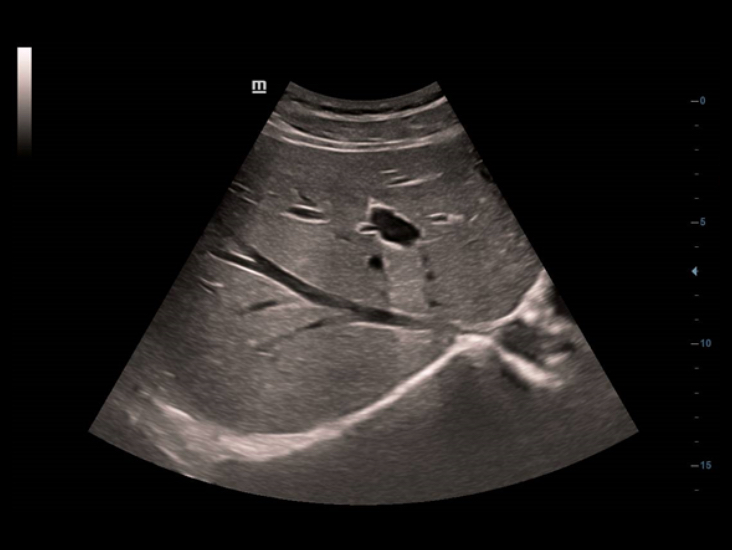

??? ?????? ??: ??? iTouch? ??? ??

Full HD ??? ?? DC-40? ?? ???? ????? ??? ??? ???? ?????. ?? ??, OB/GYN, ???? ???? Full HD ??? ?? DC-40? ???? ?? ???? ?????? ?? ?? ??? ??? ?? ??? ???? ?????.

iScanHelper

????? ??? ??? 'how & what'? ?? ???? ???? ?? ??? ?? ?????. iScanHelper?? ???? ??, ?? ??? ??, ?? ?? ?? ? ??? ??? ?? ?? ???? ????.